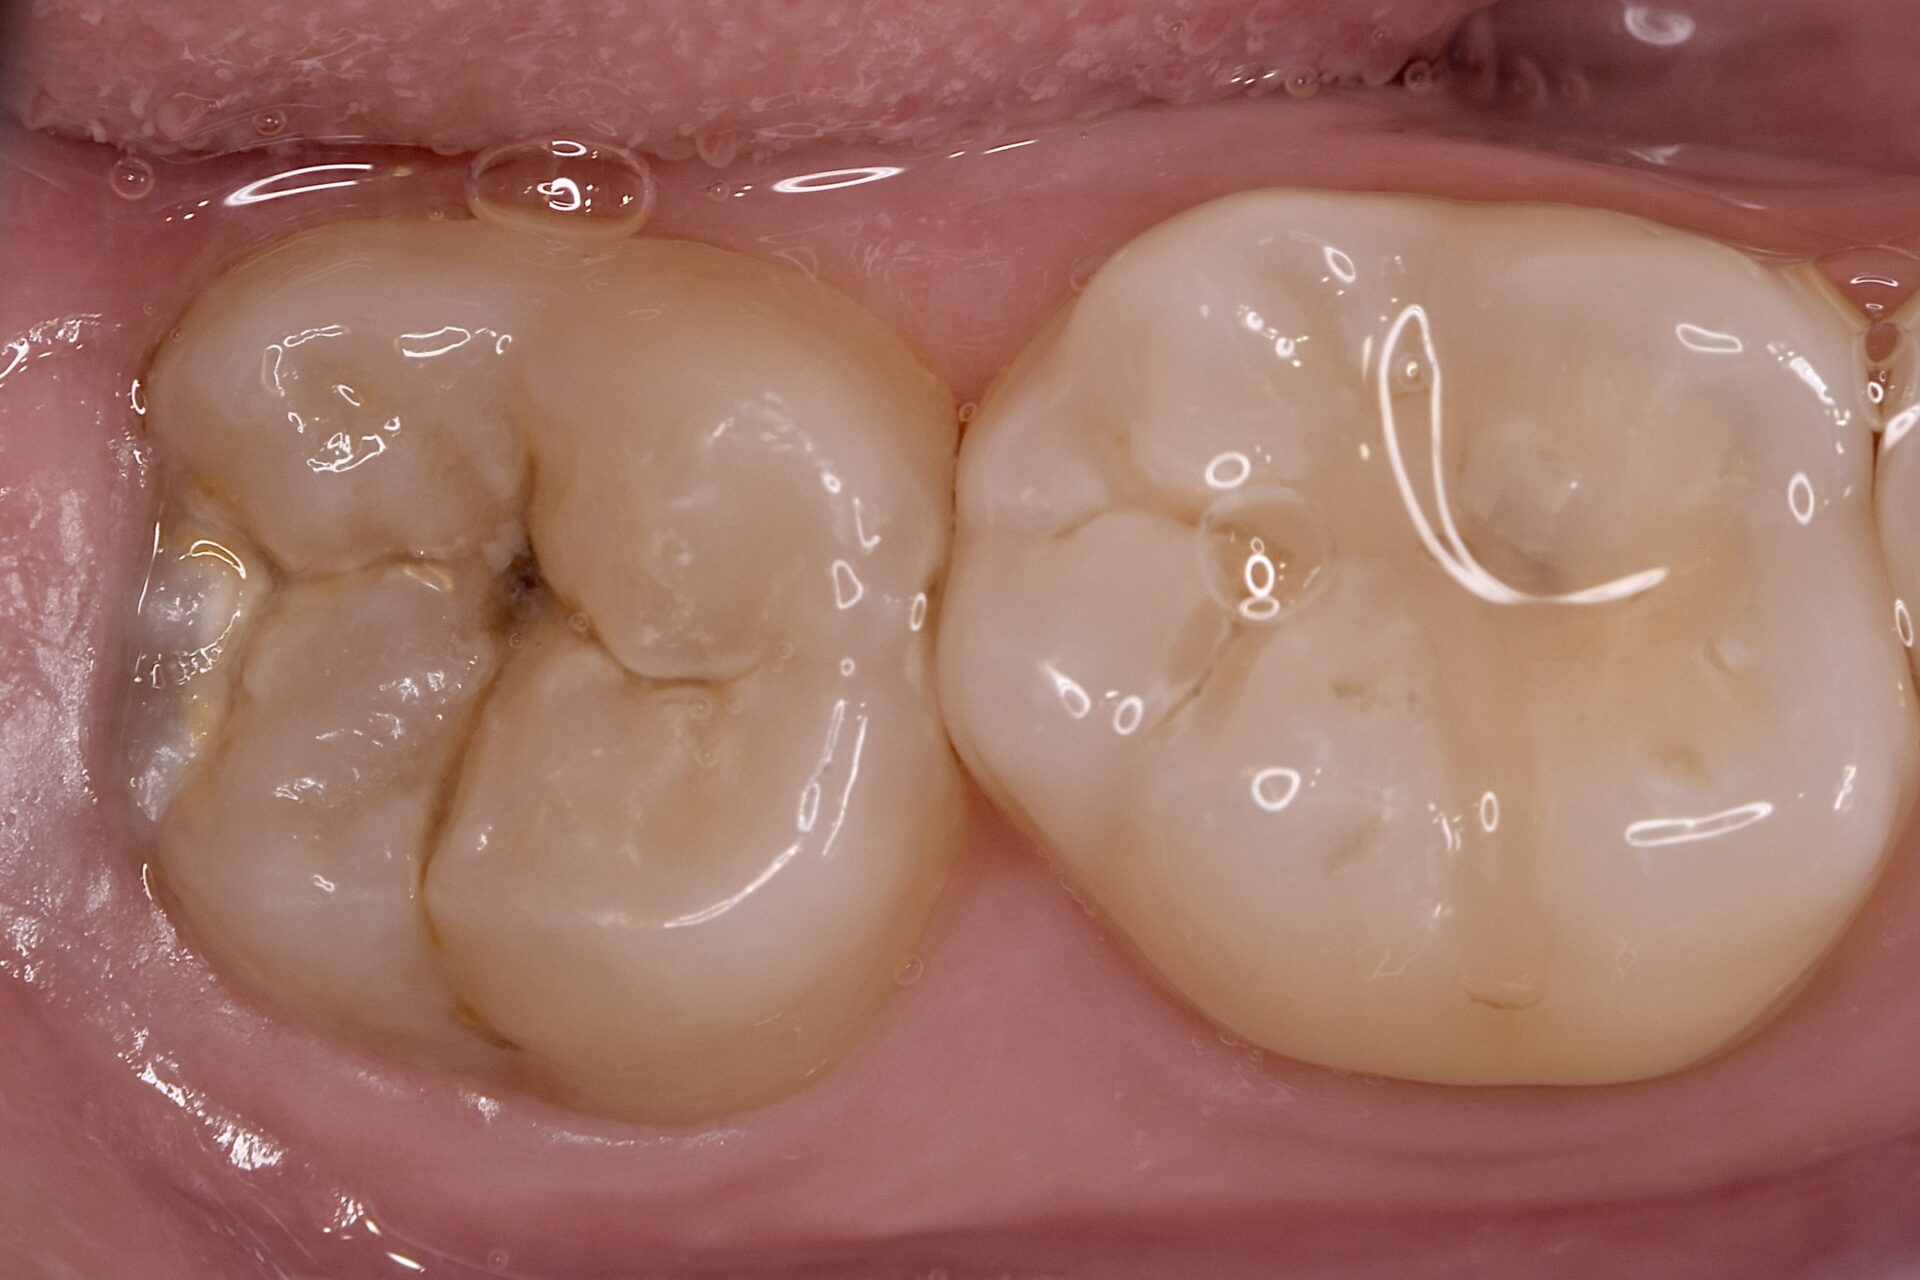

Before

| 年齢 | 20代 | 治療方法 | ダイレクトボンディング |

| 性別 | 男性 | 通院回数 | 2回 |

| 主訴 | むし歯を治したい | 費用 |

115,500円(税込) |